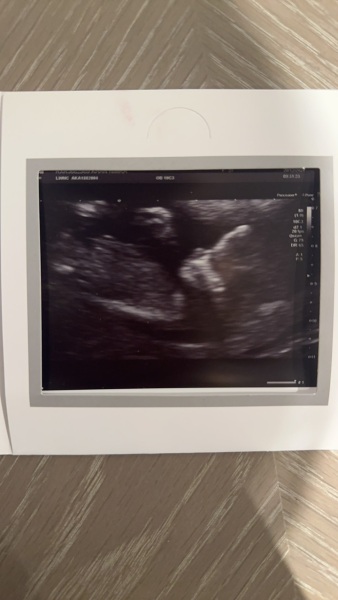

Hi Guys, I had my 12 week scan yesterday the baby was not very cooperative but can we tell the gender? I have been told boy by friends based on the skull and nub (which I cannot see) but when trying to measure the nub I am getting girl?

For reference I am 12 week 6 days here

I have added the photo of the scan any advice is appreciated (my private scan is in 3 weeks and I simply cannot wait!)

Skull looks like a boy's.